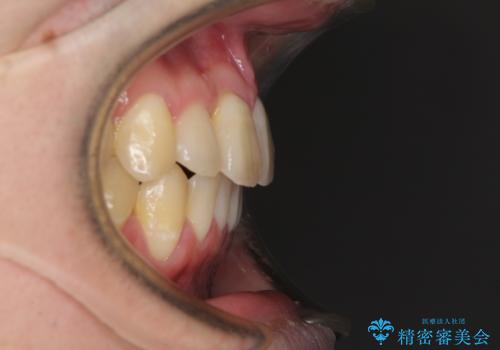

前歯のクロスバイト インビザラインによる矯正治療

- 上下のクロスバイトと前歯のデコボコを気にして来院された患者様です。

インビザラインを用い、IPR(歯と歯の間を削る)と歯列全体を拡大させることで、歯並びを整えていくこととしました。

奥に位置していた上の前歯が下の前歯を乗り越える際、奥歯でものを咬むことができず、辛い時期が続きました。